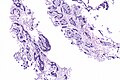

AdCC trachea - low mag.